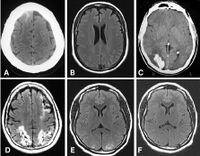

Radiation therapy has benefited greatly from technological advances over the past two decades, resulting in a wide variety of available delivery methods: Intensity-modulated radiation therapy (IMRT) utilizing techniques to quantify the critical normal tissue doses; Image-guided radiotherapy (IGRT) utilizing real-time imaging for treatment localization during radiotherapy; Stereotactic radiosurgery (SRS) delivering of a large dose per fraction to treat focal brain lesions and its extension, stereotactic body radiation therapy (SBRT), to treat focal lesions in the lung, spine, liver, pancreas, prostate and all parts of the body; Particle beam radiotherapy utilizing protons, neutrons or other heavy particles; Brachytherapy placing sealed radioactive sources near the tumor; Intraoperative radiotherapy (IORT) delivering to the surgical bed after removal of the tumor or to the tumor itself at the time of surgery; Unsealed sources delivering a radiopharmaceutical orally or parenterally; and Hyperthermia adding of heat to radiotherapy.